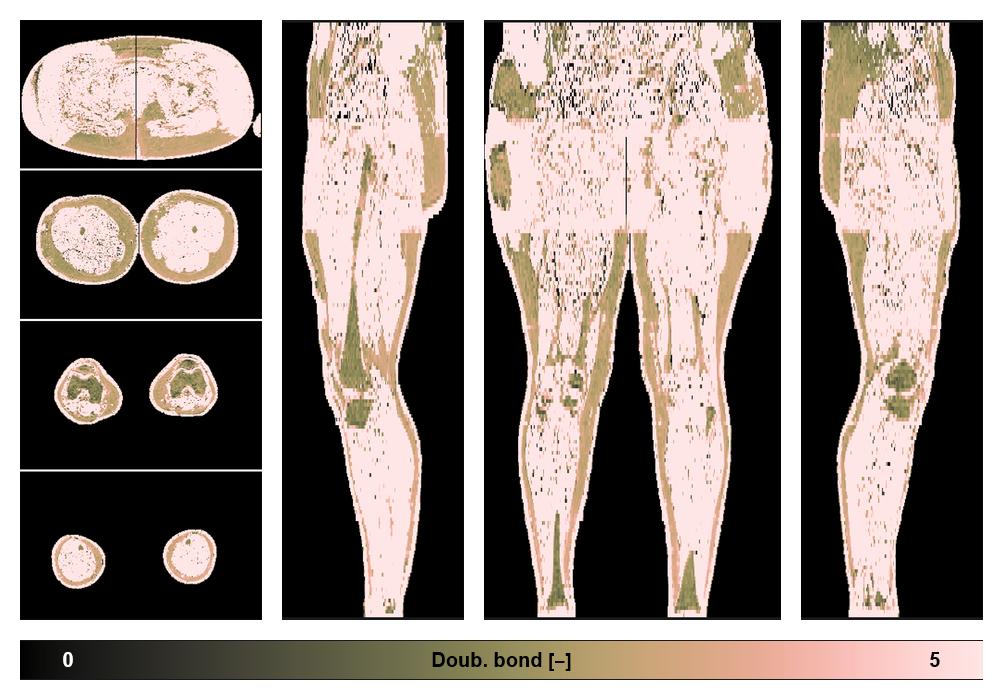

• Number of double bonds in subcutanious fat

Number of double bonds in subcutanious fat.